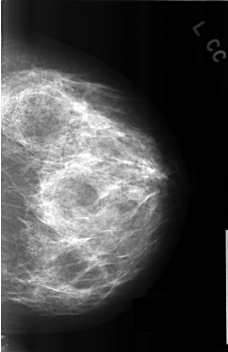

C_0309_1.LEFT_CC

LEFT_CC LINES 4576 PIXELS_PER_LINE 2960 BITS_PER_PIXEL 12 RESOLUTION 50 NON_OVERLAY